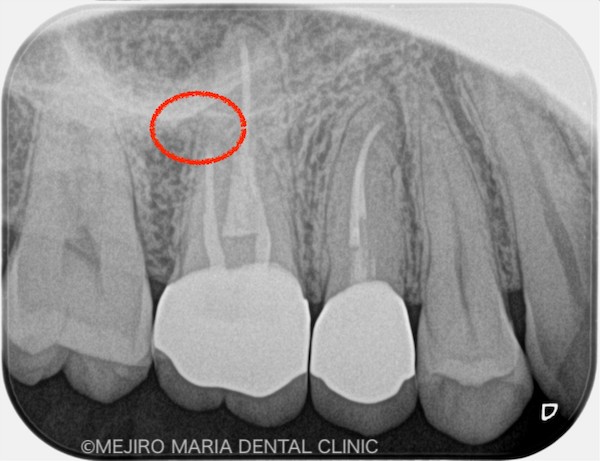

赤丸は病変が消失したところ

術後3ヶ月の経過は良好だったため、最終補綴処置を完了し、その後1年間、経過を確認しました。その結果、右上6番の歯に確認できていた病変も消失し、現時点は予後良好と判断しています。